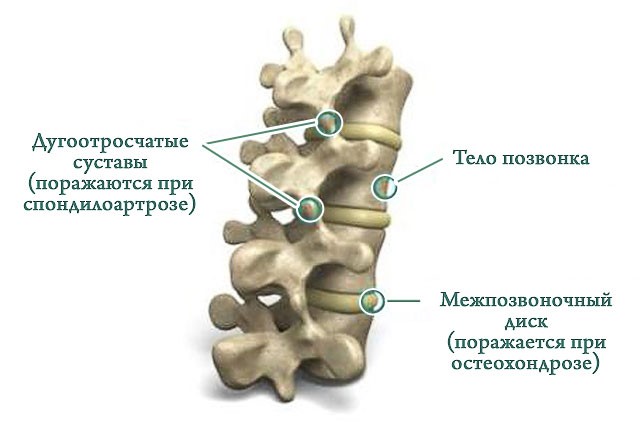

Структура и анатомия синдесмоза: научные иллюстрации